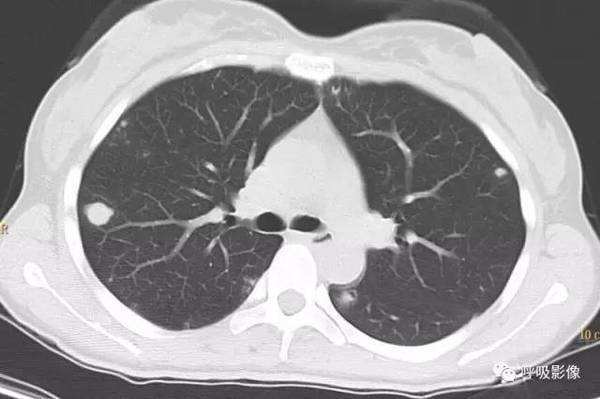

分析: 恶性肿瘤的肺转移率高达40%-50%,80%-90%为多发转移,约10%-20%为局限性或孤立性病灶,影像诊断较为困难。某些原发瘤易造成孤立结节肺转移,包括结肠癌(特别是直肠乙状结肠区)、肉瘤(特别是起源于骨的肉瘤)、肾癌、膀胱及睾丸恶性肿瘤、乳腺癌以及恶性黑色素瘤等。

孤立性肺转移瘤 多为肺血行转移的一个阶段,因为肺血供特点,其分布是右肺略多于左肺、下肺多于上肺、几乎都分布于肺野外带及胸膜下肺组织。

孤立性肺转移瘤受血行转移过程及原发肿瘤的病理及生物学行为双重影响,表现形式多样,和众多的肺内孤立性结节鉴别较为困难。